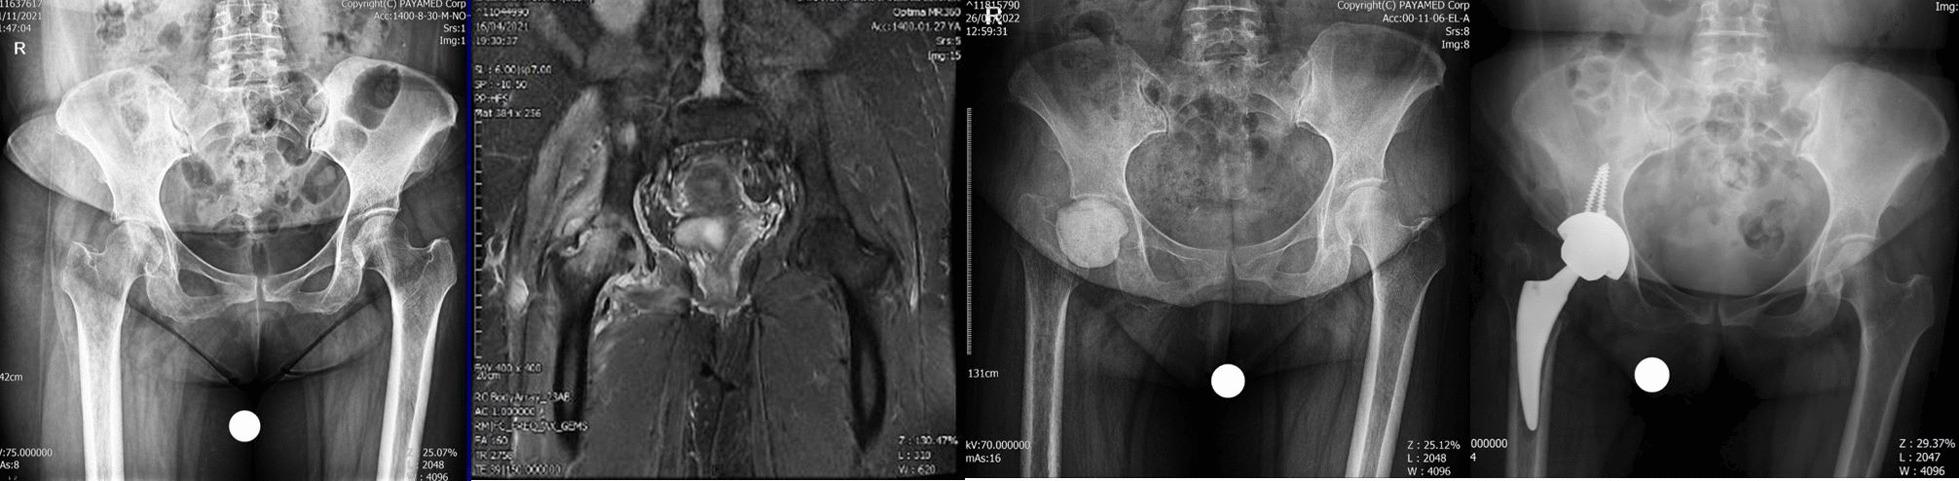

近期 COVID-19 感染患者髋关节合并感染性关节炎和股骨头无菌性坏死:一个警示性报告。

Concomitant septic arthritis of the hip joint and femoral head avascular necrosis in patients with recent COVID-19 infection: a cautionary report.

At present, concomitant avascular necrosis (AVN) of femoral head and septic arthritis (SA) as a sequel of COVID-19 infection has yet not been documented. By large-scale use of life-saving corticosteroids (CS) in COVID-19 cases, our aim is to warn of the occurrence of hip joint infection in these patients.

We report a series of five cases in which patients developed septic arthritis concomitant with AVN after being treated for COVID-19 infection. The mean dose of prednisolone used in these cases was 1695.2 mg. The time period of onset of hip symptoms in our cases from the beginning of the COVID-19 infection was 56 days in the first case, 43 days in the second case, 30 days in the third case, 29 days in the fourth case and 50 days in the last case, with an average time of 41.6 days. All patients underwent surgery depending on the extent of articular cartilage damage by direct anterior approach.

RESULTS

Clinical and laboratory symptoms improved significantly in all patients. The mean visual analogue pain score of the patients decreased from 9.4 (9-10) before surgery to 2.8 (1-4) after 1 week of operation.

CONCLUSION

In any patient with the history of COVID-19 infection specially those who have been treated with corticosteroid as one of the medications prescribed during the disease, any joint symptom specially in the hips should draw our attention to the joint infection, and with timely diagnosis and surgery, their hip joint can be saved.